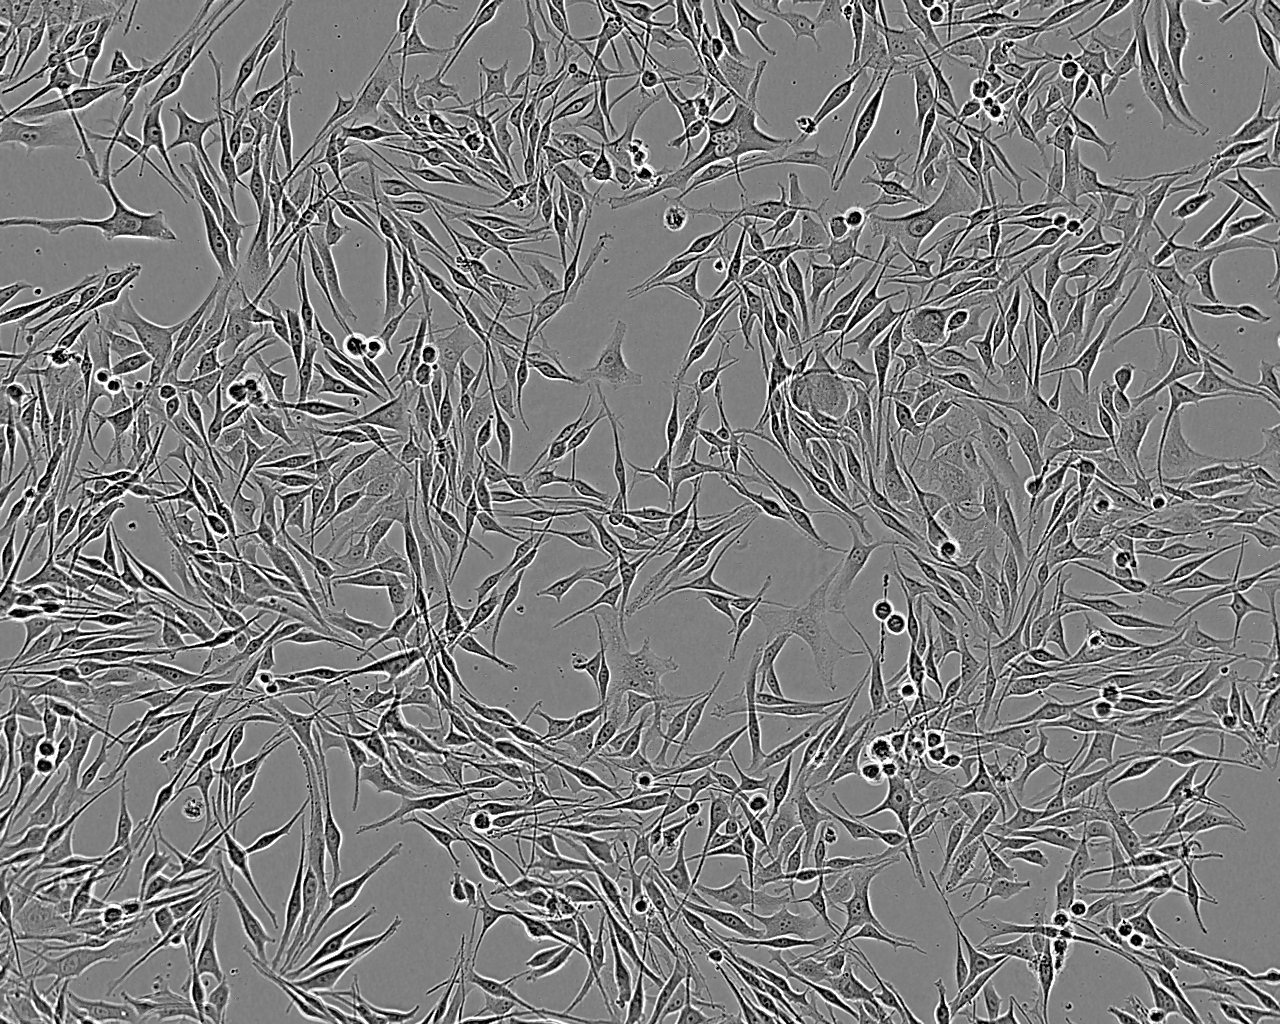

Derived from a brain metastasis of a 62 year old male with melanoma. The cells bleb during culture.

Images